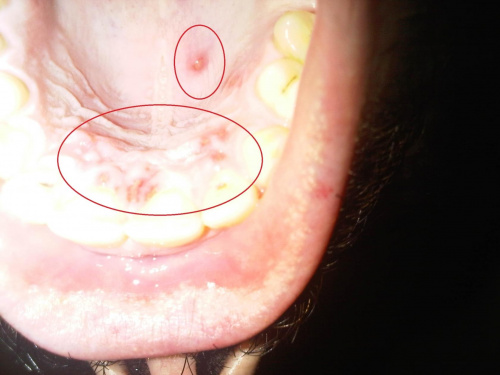

Przyczyny czerwonych krostek pod językiem

Witam. Skąd mogą się wziąć czerwone krostki pod językiem, co to może być? Żaden lekarz nie ma pojęcia a byłem już u czterech.

Niebolesne krosty na śliniance podjęzykowej

Witam. Czy krostki pod językiem - niektóre czerwone, niebolesne (a konkretnie - na sliniance podjezykowej, tj gdy jezyk lezy luźno to widać, że to jest ślinianka, a jak rozciągam język to ślinianka "rozwija" się pod nim) niektóre jakby takie pęcherzyki,... Witam. Czy krostki pod językiem - niektóre czerwone, niebolesne (a konkretnie - na sliniance podjezykowej, tj gdy jezyk lezy luźno to widać, że to jest ślinianka, a jak rozciągam język to ślinianka "rozwija" się pod nim) niektóre jakby takie pęcherzyki, mogą być wynikiem grzybicy jamy ustnej bądź haczenia o ostre zęby? Żaden lekarz nie był mi w stanie powiedzieć co to może być.